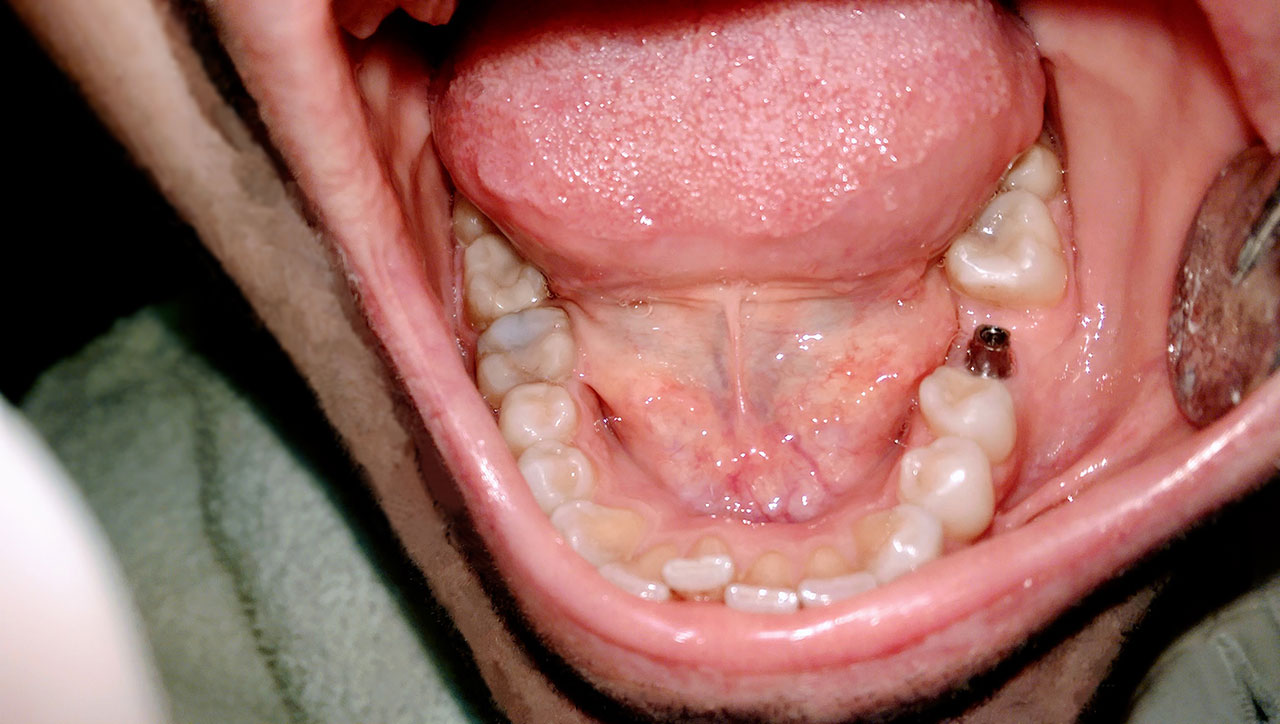

2 nap alatt varázsoltuk ezt a szép esztétikus alsó, felső körhídat implantátumokkal megtámasztva a korábban elhanyagolt szájba. Az 1. nap 26 fogat távolítottunk el, mert annyira rossz állapotban voltak, és rögtön azonnal terhelhető IHDE svájci implantátumokat raktunk be, fentre 8, lentre 6 darabot. A sebeket összevarrtuk és intraorális szkennerrel digitális lenyomatot vettünk. 2 nap múlva pedig beragasztottuk a kész PMMA műanyag körhidakat. Dr. Kelemen Péter és a Symbion Fogtechnika munkája.